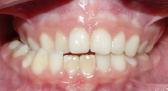

5 MORDIDA CRUZADA ANTERIOR

Cuando los incisivos superiores muerden por detrás de los inferiores.